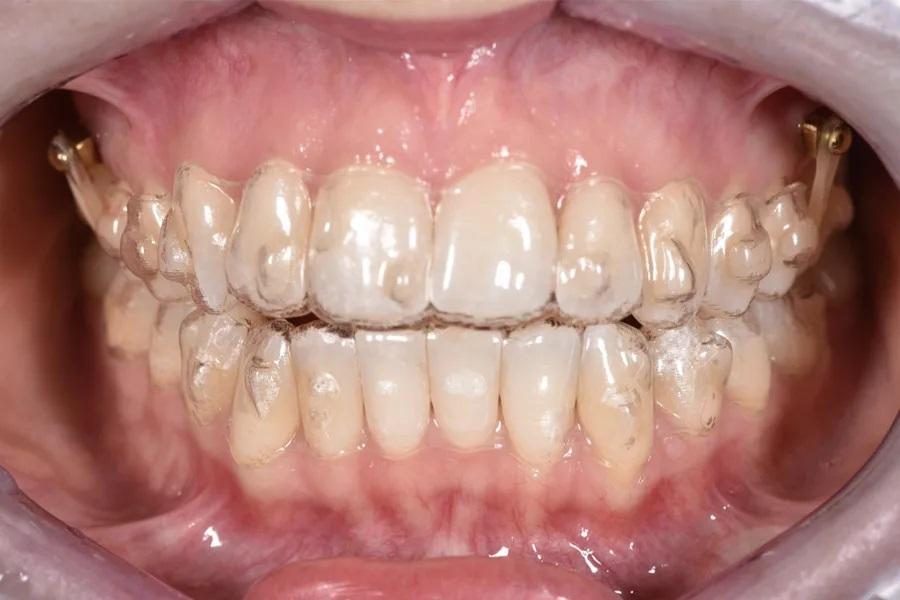

Фото 10. Окклюзионный вид интрузии с опорой на ВОУ при использовании элайнеров и эластиков; показаны расположение, биомеханика и используемые аппараты.

Фото 11. Фронтальный вид интрузии с опорой на ВОУ при использовании элайнеров и эластиков; показаны расположение, биомеханика и используемые аппараты.